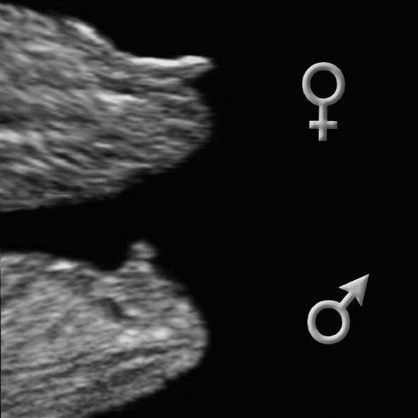

Изображение Natalia, вот фото 12 нед 4 дня, теперь смотрю на фото и думаю, девчачий ли бугорок, и бугорок ли вообще))

05.05.2022

Ольга , фото конечно не в таком срезе как надо ,должен быть четкий профиль . Если по этому фото то бугорок девчачий .

06.05.2022

Natalia, это с видео скрин сделала)) головой вертел малыш и спинкой поворачивался, вот выловила)

Изображение Вот такой скрин есть

Ольга , на всех фото какое то лежачие положение бугорков )))

Natalia, весь бб перерыла, фото у многих видела с узи, вроде похоже, но есть и где с мальчиком похожи бугорки 🙈

Ольга , там на фото 2 бугорка как бы один чуть прозрачный и белый , белый это кость а вот чуть прозрачный выше это прям как у меня бугорок

Natalia, ага, поняла, но вроде вверх ничего не торчит как у мальчика)) буду надеятся🙏🤞😌🤞

Ольга , да не торчит ☺